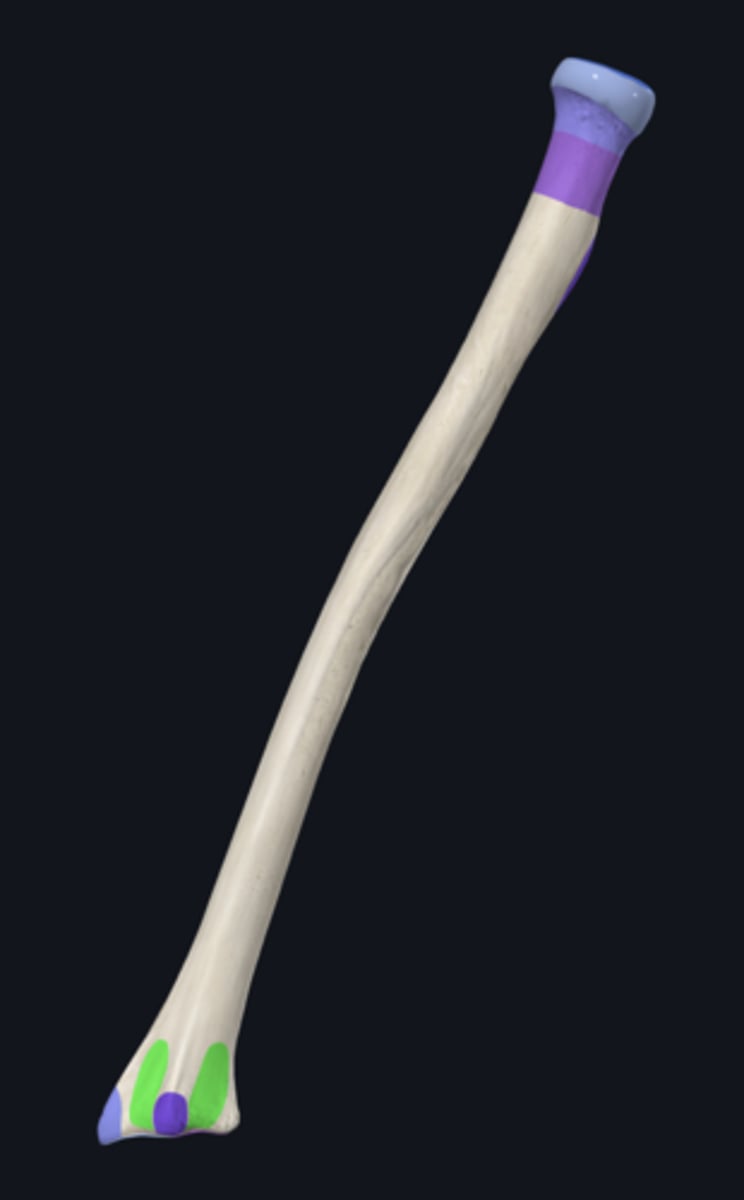

body of ulna

distal part of ulna

proximal part of ulna

anterior border of ulna

anterior surface of ulna

interosseous border of ulna

medial surface of ulna

posterior border of ulna

posterior surface of ulna

supinator crest

articular circumference of head of ulna

articular facet of head of ulna

coronoid process

head of ulna

olecranon process

radial notch

sublime tubercle

supinator fossa

trochlear notch

tuberosity of ulna

ulnar styloid process